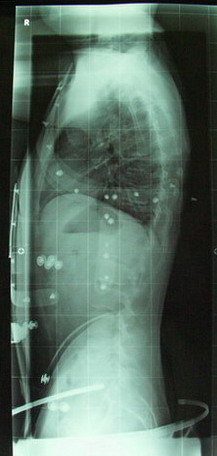

Dr. Hoffmann meinte vor dem Röntgen, das er mich auf 50 Grad schätzt.

Das die 64 Grad optisch nicht gleich zu erkennen sind hängt vielleicht mit meiner Größe zusammen (momentan 1,85 m Tendenz steigend

) und das ich keine ausgesprochenen Keilwirbel sondern eher eine "harmonische" Krümmung habe.

möchte euch meine Neuigkeiten mitteilen. Hatte gestern meine Höllenfahrt und wurde angenehm überrascht. Als erstes hat Rahmouni mein Korsett ordentlich aufgepeppt so das ich nach 15 min im Auto echt die Zähne zusammenbeißen musste. Aber die Mühen haben sich gelohnt:

Von 64 Grad vor der Behandlung hat sich meine Wirbelsäule auf 34 Grad im Korsett verbessert. Ich kann das noch nicht ganz fassen und bin überglücklich. Selbst wenn ich einige Stunden das Korsett nicht trage und mich dabei viel bewege prägt sich der Rundrücken lang nicht mehr so stark aus wie früher.

Das ist die Verbesserung die für mich zählt. Mal sehen was langfristig möglich ist. Demnächst gehe ich erstmal nach Bad Salzungen und lerne Schroth.

Röbis sind angehängt!

- nach 4 Wochen im Korsett

Tragzeit: täglich 10 Std - Röntgen34Gradklein.jpg (29.35 KiB) 8076 mal betrachtet

- vor Beginn der Behandlung

- Röntgen64Gradklein.jpg (26.84 KiB) 8076 mal betrachtet

noch 8 Grad und Du hast die 100% Korrektur in Deinem Alter.

Und selbst wenn Du die 34 Grad bis 55 Jahre nur halten kannst, bist Du dann im Normalzustand.

Ist das zweite Röbi bei Dr. Hoffmann und das erste woanders gemacht worden?

Sind ja sehr grosse Qualitätsunterschiede, beim ersten könnte ich den Winkel nicht erkennen.